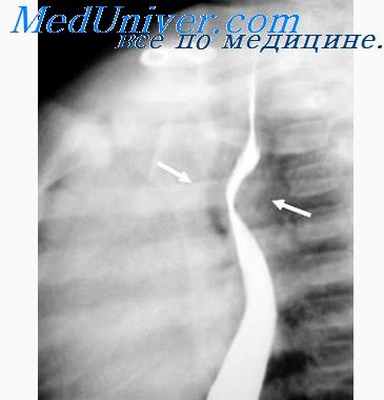

Лейомиомы. Встречаются чаще других доброкачественных опухолей [Петровский Б. В., Суворова Т. А., 1956; Каган Е. М., 1968, и др.]. Располагаются лейомиомы интрамурально на широком основании, преимущественно в средней и нижней части пищевода. Клинически долго не проявляются. Могут изъязвляться и кровоточить. При рентгенологическом исследовании определяется полуовальной формы дефект наполнения, если опухоль занимает краеоббразующее положение, либо ограниченное веретенообразное расширение пищевода при центральном положении опухоли. Контуры дефекта наполнения четкие, но не всегда ровные, так как поверхность лейомиомы может быть крупнобугристой. На уровне расположения опухоли на фоне заднего средостения нередко видна дополнительная полуовальная или полушаровидная тень той части лейомиомы, которая находится за пределами пищевода (экзоэзофагеально).

Просвет пищевода над опухолью не расширен, эластичность стенок на уровне лейомиомы всегда сохранена, а складки слизистой оболочки лишь истончаются и сглаживаются, не прерываясь на границе с опухолью.

Лейомиомы пищевода. Две трети доброкачественных опухолей пищевода составляют лейомиомы — опухоли, развивающиеся в мышечной оболочке пищевода и не вовлекающие в процесс слизистую оболочку • Симптомы. Если лейомиомы достигают размеров 5 см и более, у пациентов возникает дисфагия • Диагностика •• Контрастное рентгенологическое исследование. В стенке пищевода выявляют ограниченный дефект наполнения с гладкими краями и неизменённой слизистой оболочкой •• Эзофагоскопия необходима для подтверждения диагноза •• Биопсия противопоказана из-за повреждения слизистой оболочки, что в дальнейшем осложняет оперативное лечение • Оперативное лечение •• Правосторонняя торакотомия и энуклеация (вылущивание) опухоли из стенки пищевода без повреждения слизистой оболочки у пациентов с клиническими проявлениями опухоли •• Резекцию пищевода производят, если опухоль располагается в нижней части пищевода и произвести её энуклеацию невозможно.